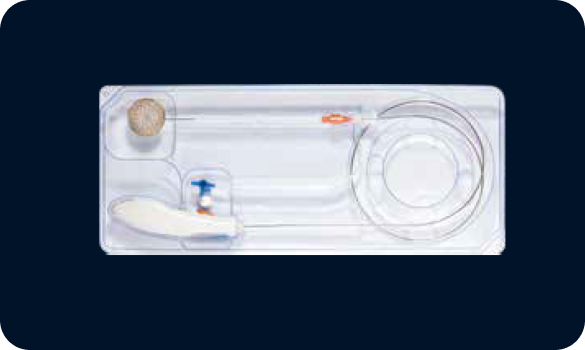

Innovative Delivery System

Pre-mounted delivery system, shorter operation time